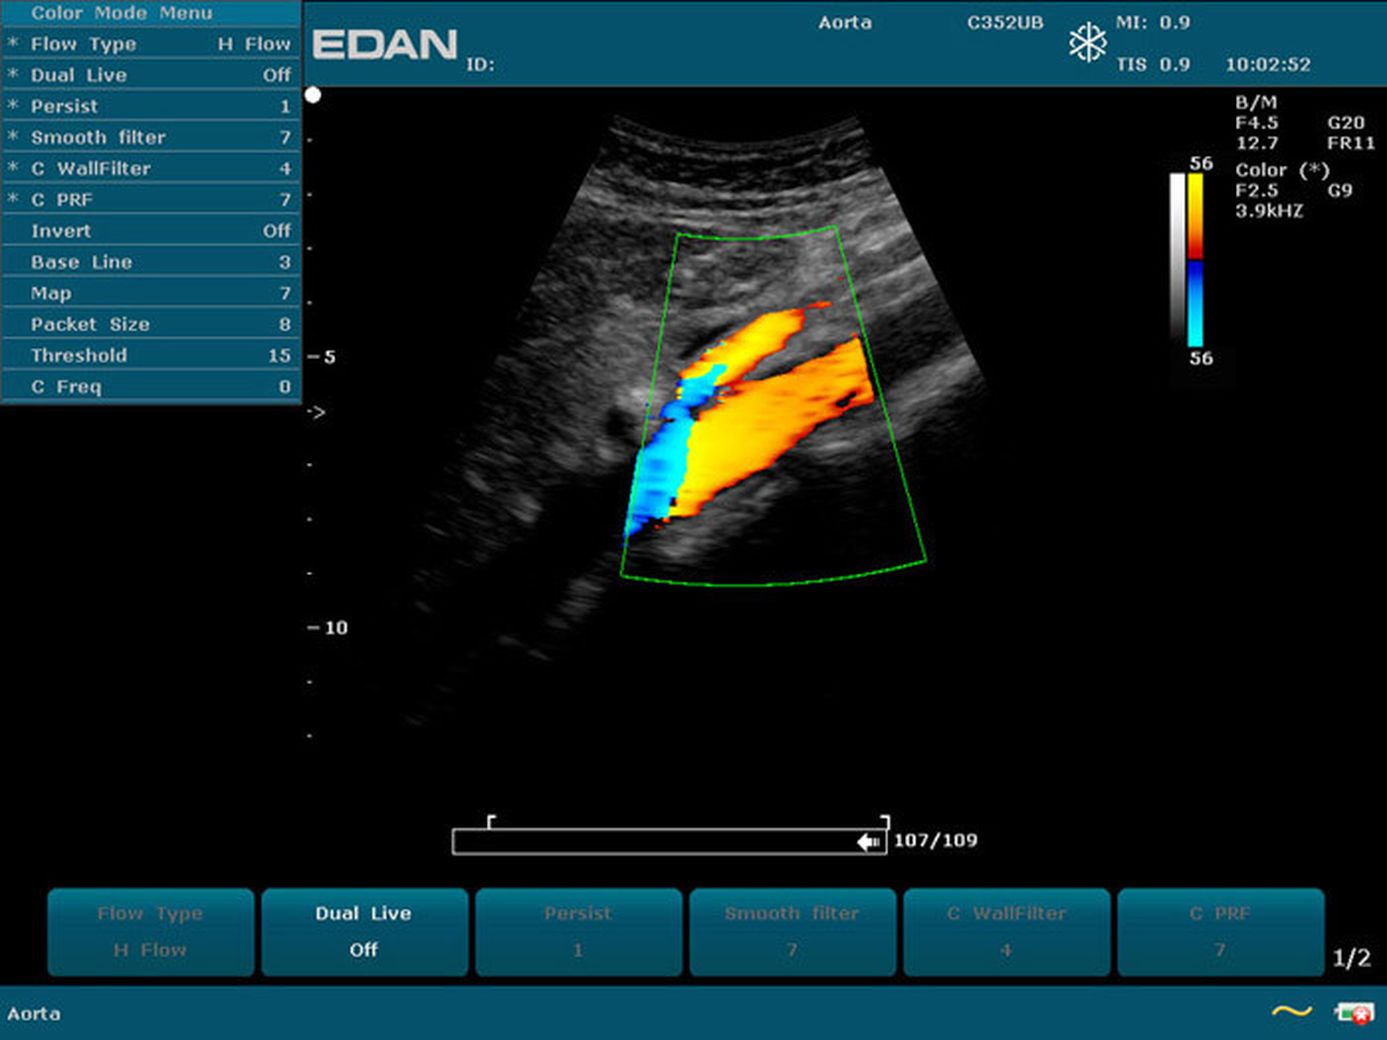

Прибор u2 143 фото